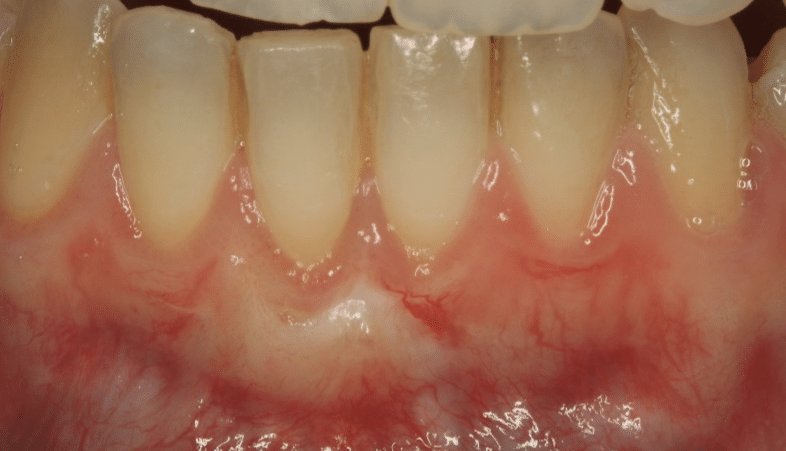

Coronally Advanced Flap with connective tissue graft

This method is commonly used to achieve total root coverage in isolated and multiple recession sites. This method requires harvesting a connective tissue graft from the palate. This graft is then sutured onto the defect, and it is subsequently covered by a coronally advanced flap.

Figure 2. Surgical management of lower anterior recession using a coronally advanced flap and subepithelial connective tissue graft.